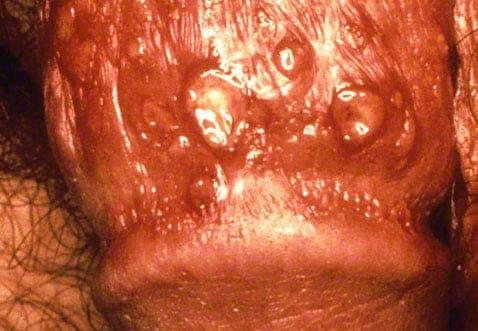

Les symptômes de l'herpès génital peuvent se développer rapidement avec des cloques (lésions) rouges gênantes et parfois douloureuses ou encore des ulcères cutanés peuvent se manifester dans la zone génitale, les cuisses, l'anus et le rectum. Le virus reste dans un nerf voisin, ce qui fait que les épidémies récurrentes se produiront toujours au même endroit.

Après avoir ressenti les symptômes du prodrome pendant quelques heures, les lésions herpétiques se développent. Ces cloques remplies de liquide démangent et peuvent également être douloureuses lorsqu'elles éclatent, laissant des plaies ouvertes facilement irritables. Vous pouvez également ressentir des douleurs lorsque vous urinez ou avoir des pertes vaginales inhabituelles pendant les symptômes actifs.

Une fois que les vésicules suintent, elles sèchent et se couvrent de croûtes après quelques jours, mais pour certaines vésicules, la guérison peut prendre de 2 à 4 semaines. Elles sont susceptibles de se fissurer et de saigner à ce stade avant que les plaies ne soient complètement guéries.

Veuillez noter : les images ci-dessous sont de nature explicite.